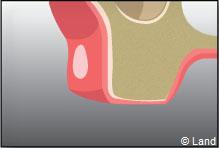

La fermeture de la cavité s’effectue souvent à l’aide de points de suture servant à réunir les bords de la gencive.